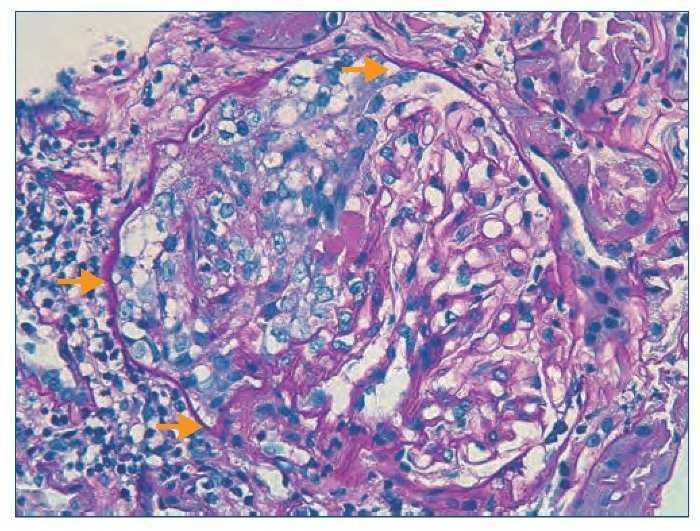

Figura 1. Histología renal caso 1 (tinción hematoxilinaeosina).

Glomérulo con engrosamiento de las paredes capilares (estrella) y presencia de trombos hialinos intracapilares característicos de la microangiopatía trombótica (flechas).